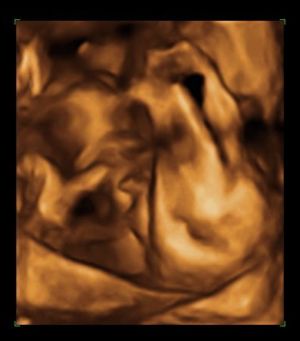

Holnap írok, addig néhány kép:

Kép 3-asban

Kép 2D-n

Kép A bizonyíték - tényleg fiú

Kép A gondolkodó

Kép A talpával is takarta magát

Kép Manó alszik